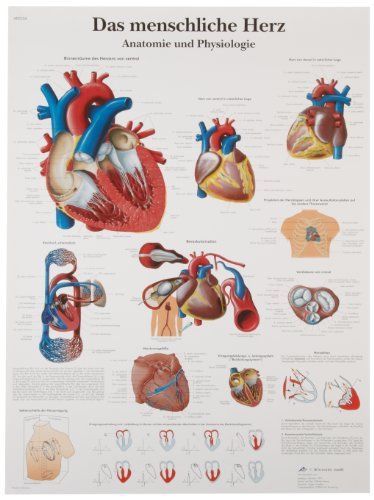

3B Scientific VR0334UU Glossy Paper Das Menschliche Herz Anatomie Und Physiologi